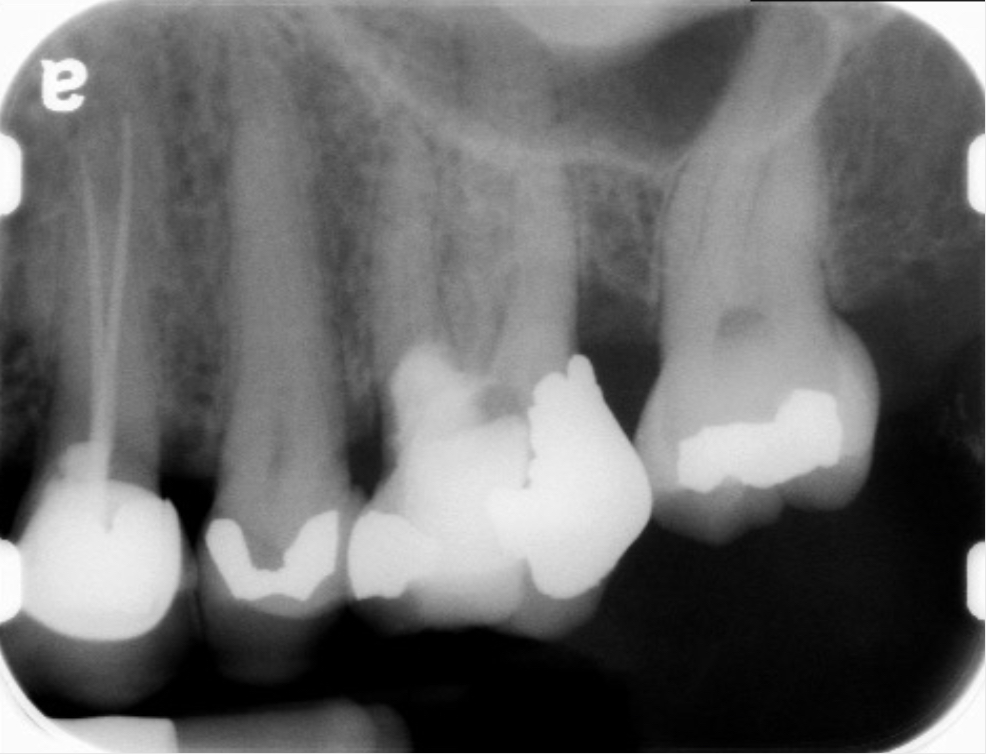

Fig 9 Preoperative radiographs showing mesial perforation.

Figure 9

Fig 10. Preoperative radiographs showing mesial perforation.

Figure 10